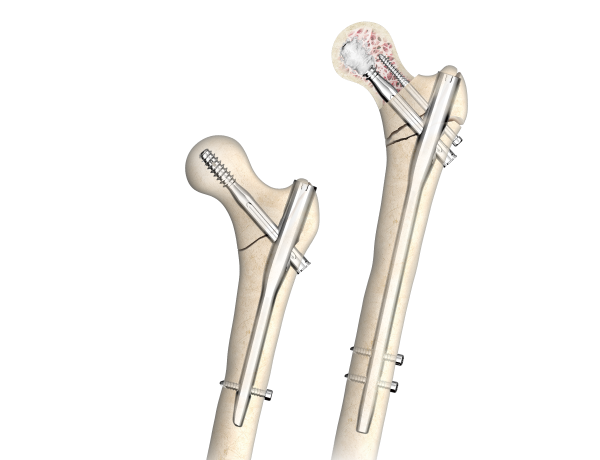

- Short Nail

- Middle Nail

- Single Lag Screw

- Double Lag Screw